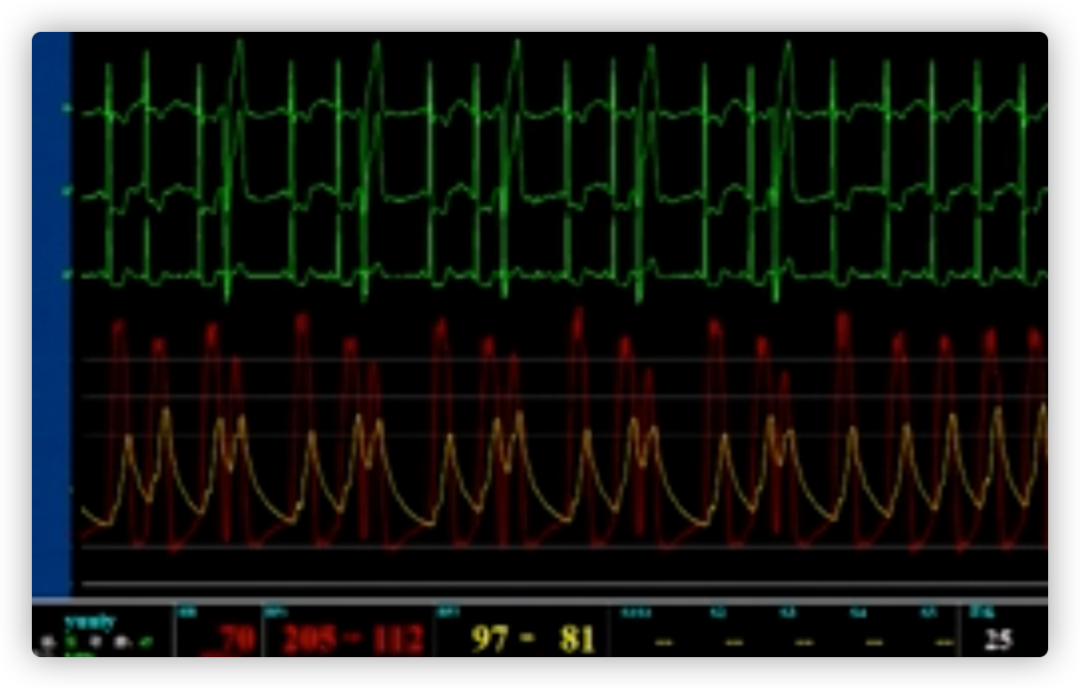

ECG术前

ECG术后即刻

ECG出院时